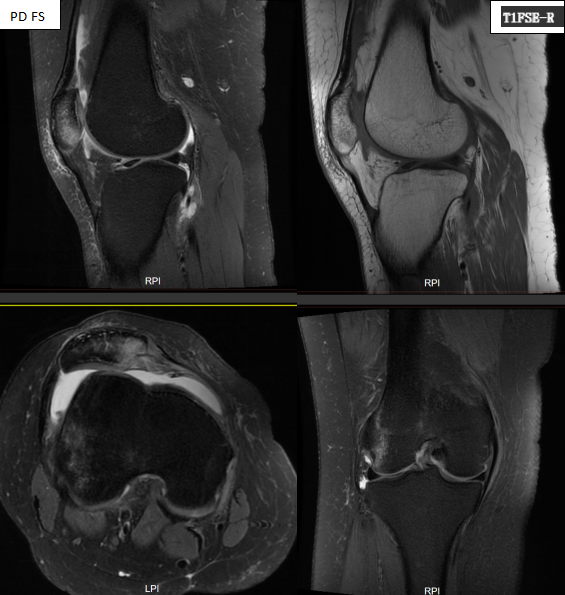

小雨随后前往南昌一脉阳光医学影像诊断中心进行了右膝磁共振检查。影像结果清晰地揭示了她膝伤的全貌:

右髌骨向外侧移位,内侧支持带肿胀,附着处髌骨骨皮质不连,髌骨内侧软骨信号欠均匀,股骨滑车浅,股骨外侧髁骨松质见片状PD压脂高信号;余膝关节构成骨未见异常信号,关节腔及髌上囊积液。

诊断结果:髌骨不稳(髌骨外移、股骨滑车发育不良),考虑髌骨脱位伴复位后,内侧支持带部分撕裂,附着处髌骨撕脱骨折,髌骨内侧软骨损伤,与股骨外侧髁对冲骨挫伤;关节积液。。